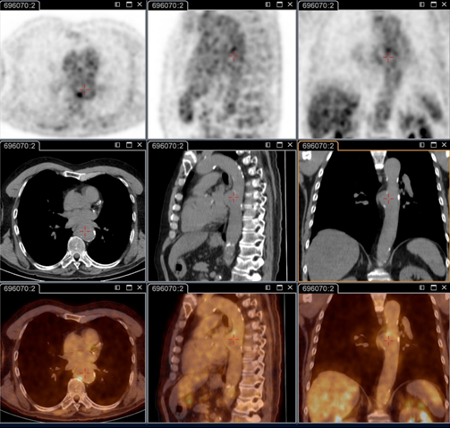

18F-ფთორდეზოქსიგლუკოზით (FDG) PET/CT სკანირება

ტესტი

კრიტიკული მნიშვნელობისაა პერსისტენტული ფოკალური ინფექციების იდენტიფიცირებისათვის.[78]

კვლევის ამ მეთოდით შესაძლებელია ენდოკარდიტის, სისხლძარღვოვანი ინფექციის, ლიმფადენიტის, ძვალსახსროვანი ინფექციების გარჩევა. ამ მიდგომის გარეშე ჩამოთვლილი მდგომარეობების იდენტიფიცირება შეუძლებელია.

ამჟამად აღნიშნული კვლევა სტანდარტული ანატომიური კვლევის მეთოდია პერსისტენტული სიმპტომების და/ან პერსისტენტულად მომატებული სეროლოგიური მაჩვენებლების და/ან სისხლის ან შრატის დადებითი პჯრ-ის მქონე პაციენტებში, ან ნებისმიერ შემთხვევაში როცა კლინიკური გამოვლინება არ შეესაბამება პირველად ინფექციას.[3]

კონკრეტულად რეკომენდებულია შემდეგი პაციენტებისთვის: მწვავე Q ცხელება პერსისტენტული I ფაზის IgG ≥1:800 და/ან ვლინდება ცუდი კლინიკური განვითარება; მწვავე Q ცხელება სისხლძარღვის გრაფტის ან ანევრიზმის ანამნეზით; ან აუხსნელი (I ფაზის IgG ≥1:800) სეროლოგიით ან პერსისტენტულ ინფექციაზე კლინიკური ეჭვის დროს.

ასევე გამოსადეგია ინფექციის იდენტიფიცირება პაციენტებში, რომელთაც აღენიშნებათ სისხლძარღვის პროთეზი და/ან ანევრიზმა. საჭიროა გადაწყვეტილების მიღება, თუ რომელ პაციენტს ესაჭიროება ქირურგია ინფიცირებული სისხლძარღვოვანი ქსოვილების ამოსაკვეთად.[Figure caption and citation for the preceding image starts]: Q ცხელების ენდოკარდიტი, PET სკანირება: 18F-ფთორდეზოქსიგლუკოზა PET/CT. პაციენტი უსიმპტომოა, ანამნეზში აქვს სარქველის პრობლემა, მომატებულია სეროლოგია. PET სკანირებით დიაგნოსტირდა აორტის ენდოკარდიტი ბუნებრივ სარქველზე, თორაკალური და წელის აორტის მიკოზური ანევრიზმებითInstitut Hospitalo-Universitaire Méditerranée Infection (პაციენტის ნებართვა აღებულია) [Citation ends].

[Figure caption and citation for the preceding image starts]: Q ცხელების აორტული მიკოზური თორაკალური ანევრიზმა - PET სკანირება: 18F-ფთორდეზოქსიგლუკოზა PET/CT. პაციენტი უსიმპტომოა, ანამნეზში აქვს სარქველის პრობლემა, მომატებულია სეროლოგია. PET სკანირებით დიაგნოსტირდა აორტის ენდოკარდიტი ბუნებრივ სარქველზე, თორაკალური და წელის აორტის მიკოზური ანევრიზმებითInstitut Hospitalo-Universitaire Méditerranée Infection (პაციენტის ნებართვა აღებულია) [Citation ends].

[Figure caption and citation for the preceding image starts]: Q ცხელების აორტული მიკოზური ანევრიზმა - PET სკანირება: 18F-ფთორდეზოქსიგლუკოზა PET/CT. პაციენტი უსიმპტომოა, ანამნეზში აქვს სარქველის პრობლემა, მომატებულია სეროლოგია. PET სკანირებით დიაგნოსტირდა აორტის ენდოკარდიტი ბუნებრივ სარქველზე, თორაკალური და წელის აორტის მიკოზური ანევრიზმებითInstitut Hospitalo-Universitaire Méditerranée Infection (პაციენტის ნებართვა აღებულია) [Citation ends].

შედეგი

დადებითია პერსისტენტულ ფოკალურ ინფექციაზე (მაგ. გულის სარქველი, ლიმფადენიტის სისხლძარღვოვანი ელემენტი, ლიმფური კვანძი, ძვალსახსროვანი ელემენტი)